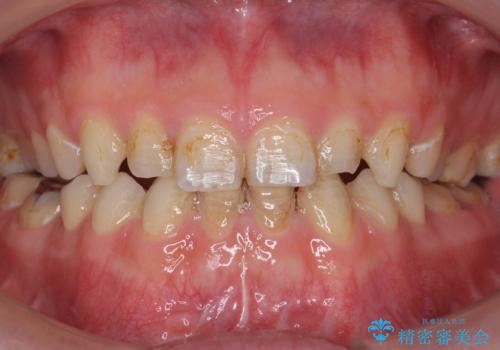

- K-POP(Kポップ)アイドルのような歯にしたいと希望され来院された患者様です。

矯正を途中でやめてしまったとのことで、歯に矯正の接着材が残っており着色も顕著でした。

奥歯の咬合面にはレジンが盛られた状態でした。

見た目と咬み合わせを改善するため、セラミッククラウンによる治療を行いました。